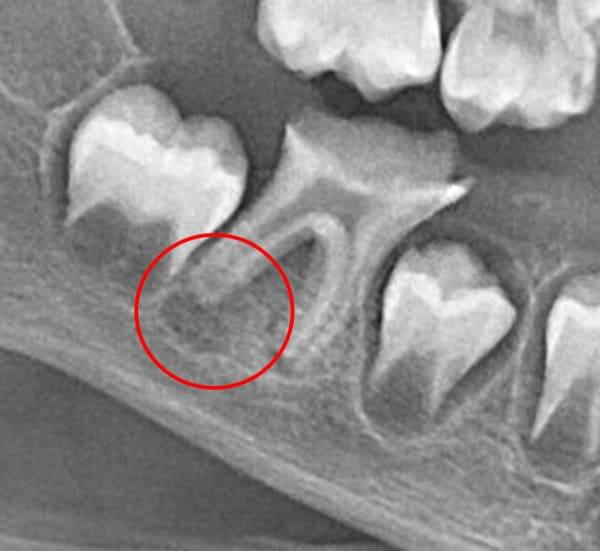

Проблема виникає, коли нерв (пульпа) постійного зуба передчасно гине від травми чи інфекції. Це критично, адже саме пульпа відповідає за ріст кореня. Без неї корінь залишається коротким і тонким. Такий зуб не може витримувати жувальне навантаження і ризикує бути втраченим. Це як дерево з великою кроною та маленьким корінцем: найменший вітер може його вирвати.

Завдяки науковим дослідженням ми знаємо, що навколо кореня зуба є стовбурові клітини. Наша методика дозволяє створити в зубі спеціальні умови, щоб ці стовбурові клітини мігрували в кореневий канал. Там вони перетворюються на клітини, схожі на клітини пульпи, і відновлюють ріст кореня — як у довжину, так і в товщину.